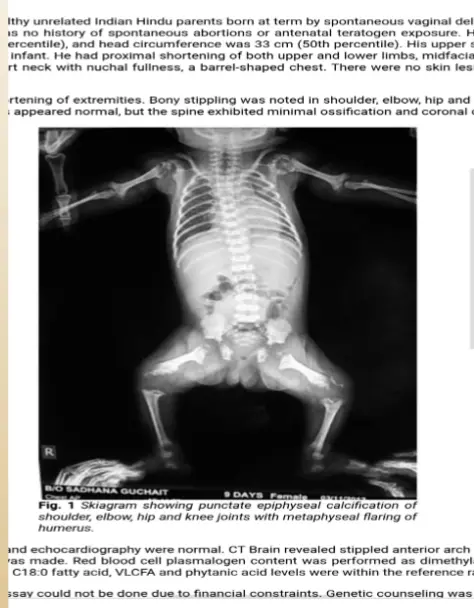

- Radiographic: Stippling of epiphyses (Chondrodysplasia punctata).

Diagnosis

Is made when the following are both present::

- The mother has anti-Ro, anti-La, or anti-ribonucleoprotein (RNP) antibodies.

- The fetus or newborn develops HB, or the newborn develops the typical rash or hepatic or hematologic manifestations in the absence of another explanation